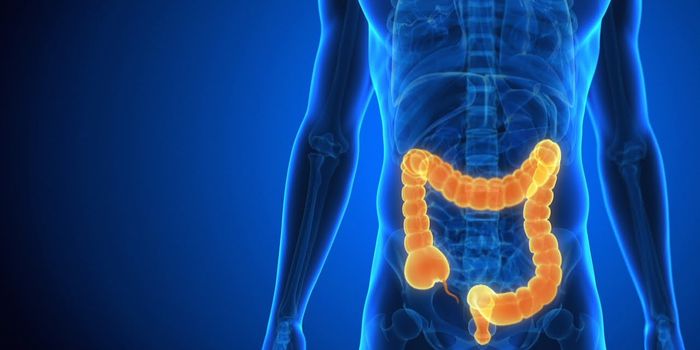

FEB 05, 2020Cell & Molecular BiologyThe contraction and relaxation of muscles in the wall of the colon helps move food along and can become dysfunctional.